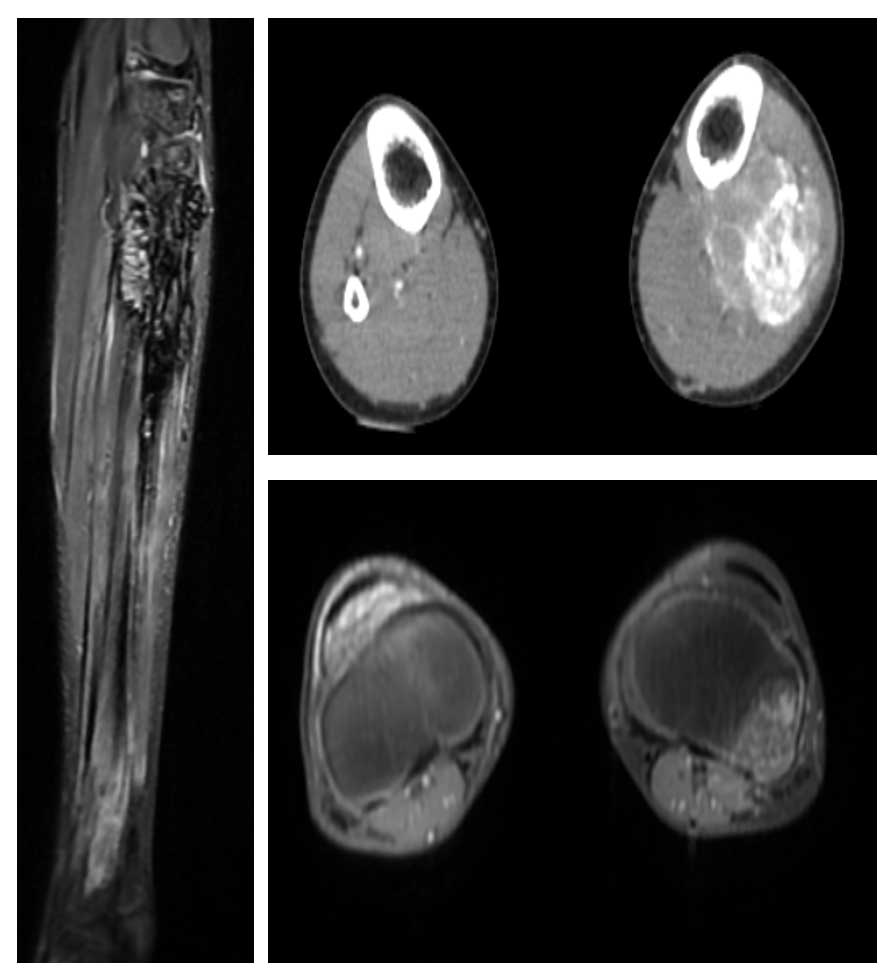

Ameliyat Öncesi: MR ve Tomografide fibulada harabiyet, yumuşak dokuya uzanım gösteren düzensiz sınırlı kitle, çevreleyen ödem ve tibiada invazyon görülmekte.